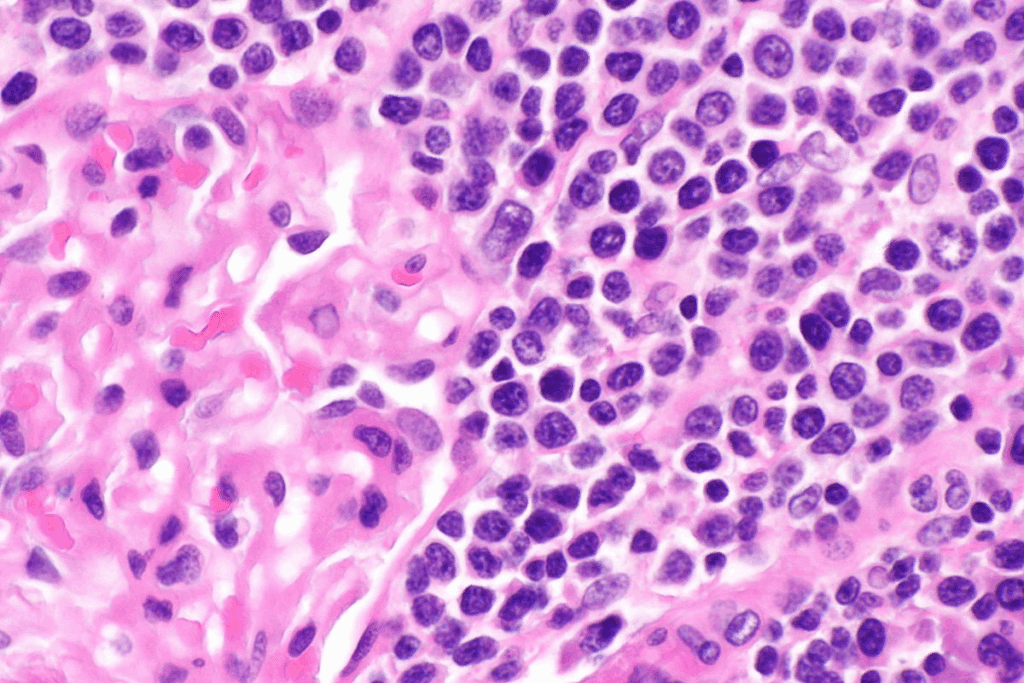

Lymphoma starts in the lymphatic system, which fights infections. It has two main types: Hodgkin and non-Hodgkin lymphoma. Hodgkin lymphoma has Reed-Sternberg cells, while non-Hodgkin lymphoma doesn’t.

Hodgkin and non-Hodgkin lymphoma differ mainly in the lymphocytes affected and the presence of Reed-Sternberg cells. Hodgkin lymphoma is marked by these cells. Non-Hodgkin lymphoma, on the other hand, is a broader category with different cell origins and behaviors.

Hodgkin Lymphoma: It usually starts in one lymph node group and spreads nearby. It’s known for Reed-Sternberg cells.

Non-Hodgkin Lymphoma: It can start in any lymphoid tissue and spread in different ways. It doesn’t have Reed-Sternberg cells and has a more varied cell makeup.